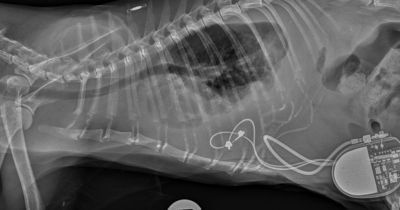

In case you missed it: RVC study reveals benefits of feline epicardial pacemakers #veterinary #cats @RoyalVetCollege

EPs improved severe heart conditions in cats.

RVC study reveals benefits of feline epicardial pacemakers #veterinary #cats @RoyalVetCollege